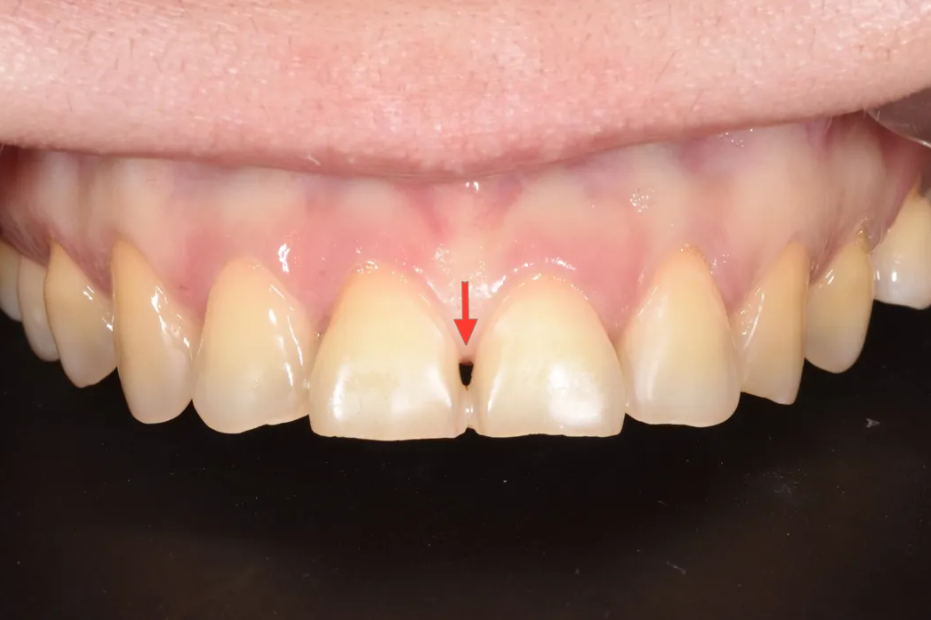

윗니 앞니 부분의 문제점

레진 수복 흔적, 색상 문제, 치아 사이 검은 삼각형, 잇몸 비대칭

가장 눈에 띄는 문제는 앞면이 레진으로 수복되어 있는 상태였습니다. 아무래도 보기에 깔끔하지가 못하였고, 치아 전체적으로도 누런 색상(Yellowish)이 심했습니다. 또한 아래위 모두 앞니 사이에 뚫린 공간이 보였고("블랙 트라이앵글"), 뿌리쪽 부분이 심하게 파여 있었어요. 잇몸의 위치도 좌우가 비대칭적이었습니다.

또한 가운데 앞니 두 개가 앞으로 돌출되어 있었는데, 특히 바깥쪽이 더 밖으로 나오면서 소위 '나비이빨' 형태를 보이고 있었습니다.

윗니 클로즈업 – 앞면 레진 수복 흔적, 누런 색상, 잇몸 라인 불균형

가운데 앞니 두 개와 왼쪽 옆 앞니의 잇몸 라인도 불균형하여 비심미적이었고, 가운데 앞니 사이에는 검은 삼각형(Black Triangle)이라 불리는 빈 공간이 보였습니다.